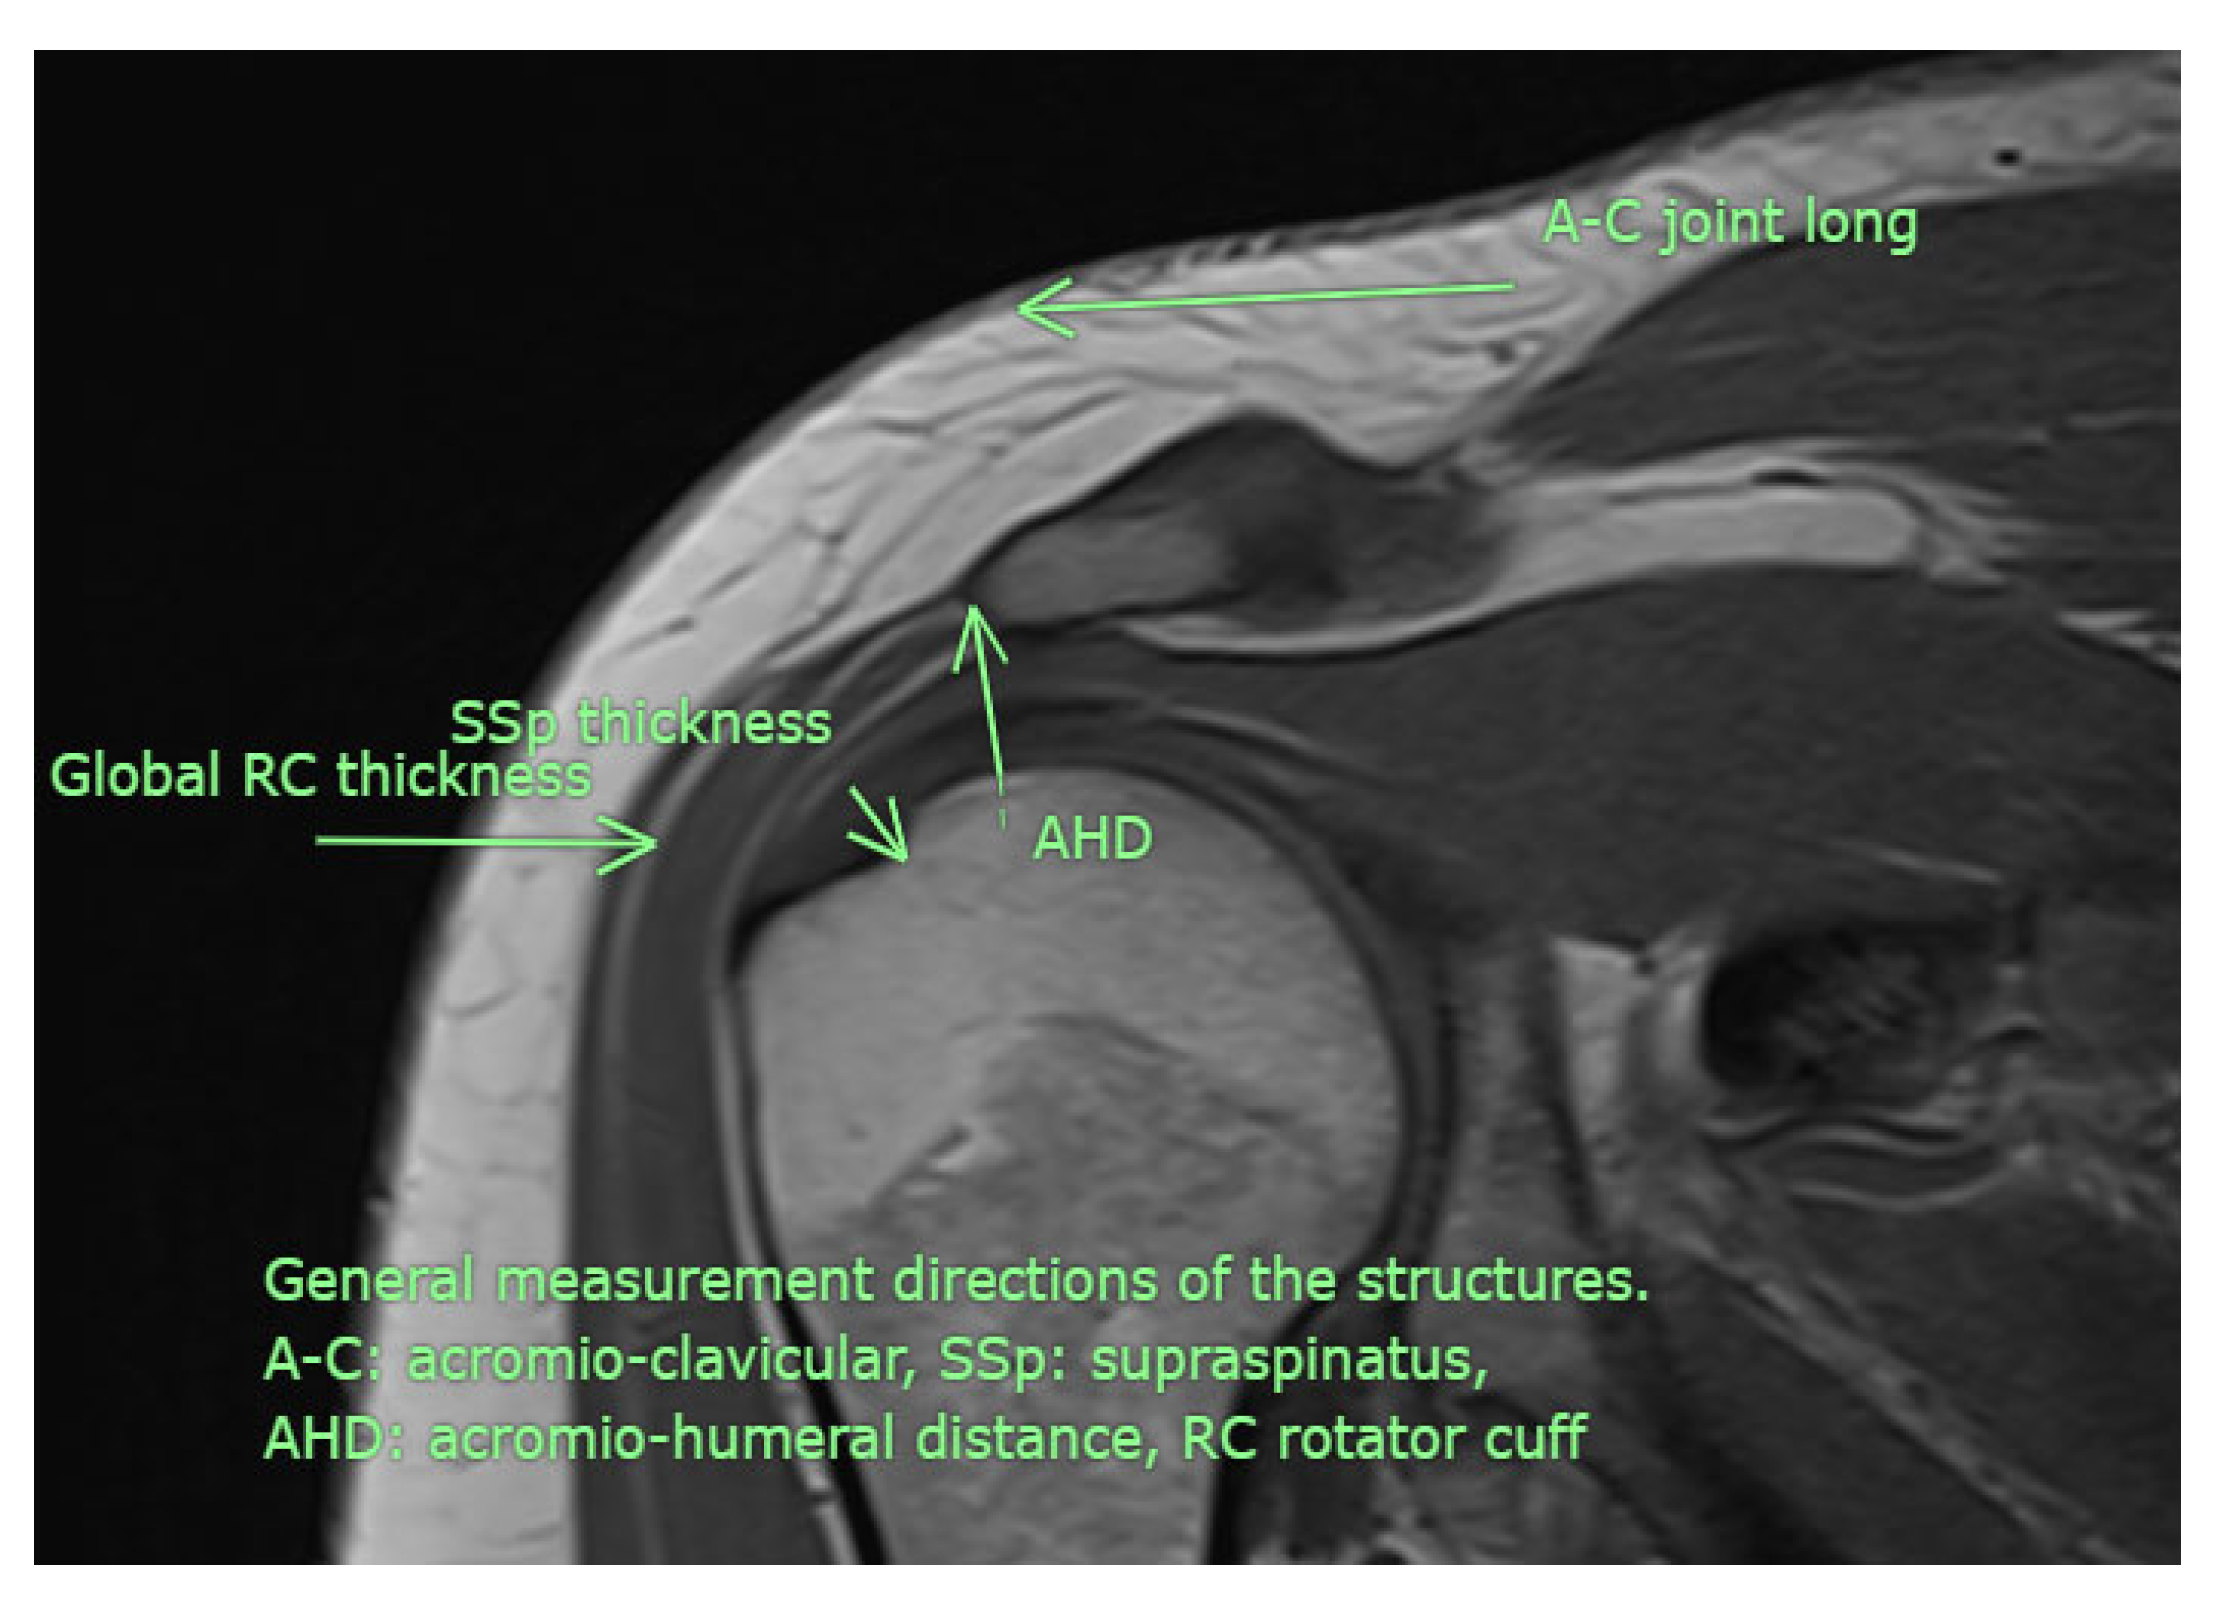

All USG evaluations were performed by a physical medicine and rehabilitation specialist with +30 years of experience in musculoskeletal USG using a GE LogiqP6 Pro device GE Ultrasound Korea, Gyeonggi, Republic of Korea and a linear transducer. Imaging was performed using standard shoulder sections while the patients were in a sitting position with an elbow flexed and an arm internally rotated and laid on the anterior thigh. We laid the probe on the coronal plane on the acromio-clavicular joint. We then moved it laterally to detect acromial-end and subacromial structures, including the subacromial bursa (SB), rotator cuff, and humeral head. Beneath the SB is the supraspinatus tendon (SSp), which attaches to the tuberculum majus of the humerus. The arm was rotated and abducted to examine the tendinous integrity and motion of the SSp. To measure the AHD and ensure standardization, a perpendicular line was drawn from the most lateral tip of the acromion to the head of the humerus, yielding an automatic value via USG-software vR2.0.5 (Figure 2 and Figure 3). In this position, we evaluated the supraspinatus and RC and measured their thicknesses on the short axis. The thickness of the SB was noted. Then, the probe was retracted, and the internal structure of the infraspinatus (Isp) and its thickness were measured. Notably, the teres minor, though difficult to discriminate, is at the posterior end of the ISp. Then, the probe was moved to the short axis to examine the biceps tendon. Here, the probe was turned to the longitudinal axis to evaluate the long biceps tendon and determine its thickness. The probe was then moved to the back side on the short axis to examine the labrum, glenoid bone, humeral head, and joint capsule. If the probe is turned longitudinally, the muscle bellies and myo-tendinous junctions of the RC muscles can be seen. Subsequently, the arm was externally rotated, and the probe was again placed medial to the biceps tendon to expose the tuberculum minus, subscapularis tendon, and anterior acromion, along with the coracoacromial ligament. Then, we positioned the arm posteriorly on the back pocket. The measurements regarding the SSp, Isp, and RC were repeated and recorded. During the examination, the acromioclavicular joint, RC tendons (supraspinatus, infraspinatus, subscapularis, and teres minor), long-head biceps tendon, SB, and related structures were evaluated in all planes. Tendon thickness, the presence of subacromial effusion, ruptures, tendinous degeneration, contour irregularities, RC integrity, and homogeneity were examined. Measurements were performed before (baseline) and after the treatment (post-tr).

Figure 2. USG AHD measurements. See text.

Figure 3. Although examined in all available directions, this MRI image illustrates the measurement sites used in the study (personal archive).